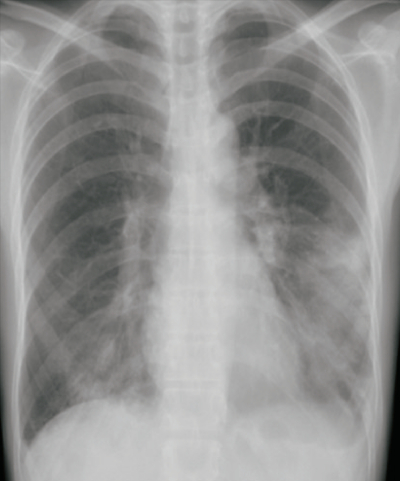

体温 37.4 ℃。脈拍 104/分、整。血圧 118/62 mmHg。呼吸数 18/分。SpO₂ 95% (room air)。左下胸部にcoarse cracklesを聴取する。

血液所見:赤血球 456万、Hb 13.0 g/dL、Ht 39%、白血球 19,800 (好中球 85%、好酸球 1%、好塩基球 1%、単球 5%、リンパ球 8%)、血小板 34万。CRP 15 mg/dL。胸部エックス線写真及び喀痰Gram染色標本を別に示す。